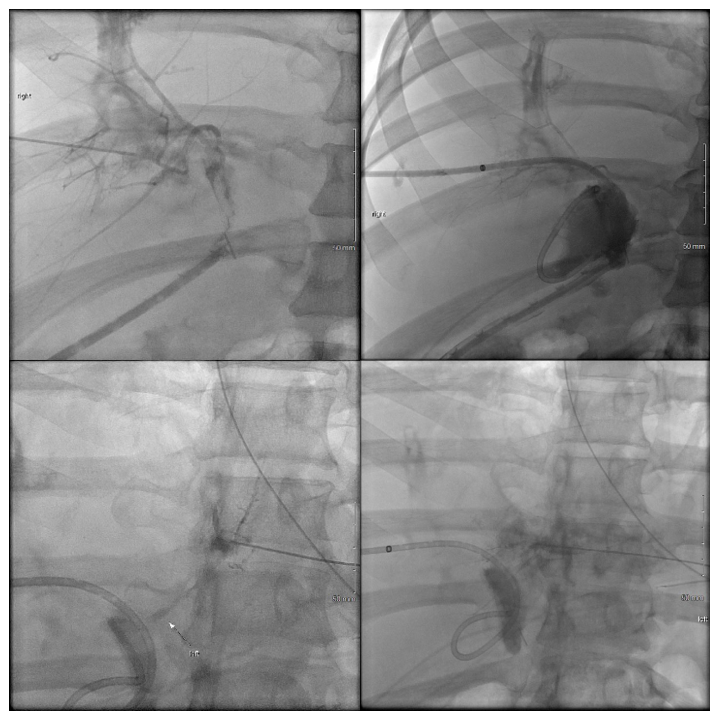

A 29-year-old male presented to an outside hospital for evaluation for abdominal pain and was diagnosed with acute cholecystitis. The patient was taken to the operating room nine days prior to presentation at our hospital for a laparoscopic cholecystectomy. Though the dissection was difficult, the case proceeded uneventfully and the patient was subsequently discharged post-operatively. The patient returned to the outside hospital on post-operative day 7 with high fevers and had a collection seen on ultrasonography, which was then identified as a bile duct leak on HIDA scan. An ERCP was performed at this time, but the biliary duct could not be cannulated due to an obstruction. The patient was brought back to the operating at this point for an exploratory laparotomy. After exploration, the surgeons identified a bile leak, but could not identify the proximal bile duct. Intra-operative cholangiogram was performed through the distal duct, which revealed flow into the duodenum, but the proximal duct could not be identified. Given the complexity of the anatomy and the case, the patient was transferred to us for further surgical management. On arrival, the intraoperative cholangiogram from the outside hospital was reviewed and a diagnosis of congenital agenesis of the common bile duct as suspected as flow through the ligated cystic duct went directly into the duodenum. At this time, Interventional Radiology (IR) was consulted to perform at PTC to review the biliary anatomy and create a road map for further repair. However, only the right hepatic system could be catheterized as the left hepatic duct was too small (Figure 2a). The cholangiogram through the right PTC showed a large bile leak, but no extra-hepatic ducts could be identified at all. Given these findings, the patient was then taken to the operating room for exploratory laparotomy. Upon examining the surgical site, the distal bile duct was significantly dilated to 9-10 millimeters in diameter. Proximally, the right PTC catheter placed by IR was emerging from the intra-hepatic right biliary system and further exploration did not reveal any intra-hepatic biliary ducts from the left or any extra-hepatic ducts. A complete portahepatis lymphadenectomy and dissection with skeletonized hepatic artery and portal vein was performed in an attempt to localize the left intra-hepatic duct and right extra-hepatic duct to no avail. It was suspected that the patient had variant anatomy with common bile duct agenesis with the left hepatic duct connecting to the right hepatic duct high in the liver parenchyma. Given this, continuity was restored to the biliary tree via a hepaticoportal enterotomy, or Kasai procedure. The tissue around the porta hepatis and the right PTC wrapped around an enterotomy in a two layer anastomosis. The patient was managed for the first three post-operative days in the intensive care unit before being transferred to the surgical floors where his recovery continued before ultimately being discharged. Subsequent follow-up appointments revealed adequate patency of the right-sided biliary catheters and ultimately, dilation of the left sided biliary system to permit cannulation and drainage into the intact hepaticoportal enterostomy (Figure 2b and 2c). Clinically, the patient remains stable and with unremarkable laboratory results 18 months from surgery.

Figure 2a: Initial cholangiography on presentation on 5/14/2017 for Case 2. From top left clockwise: cholangiography showing intact right hepatic duct system with distal extravasation of contrast at ligated common hepatic duct, insertion of percutaneous trans-hepatic catheter with flow into the jejunal limb, collapsed and inaccessible distal left hepatic duct system, and collapsed and inaccessible proximal left hepatic duct system.